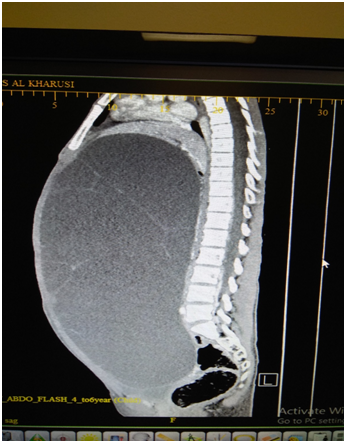

BA, a 12 years old girl was admitted through the ER, for inability to lie flat on the bed for approximately two weeks associated with some reduction in appetite in the preceding month. She had no bowel or urinary symptoms; and her LMP was on the day of presentation; with menarche 11months earlier. She denied any history of jaundice or bleeding disorder in the past. She weighed 39.7 KG, which was in the 3rd centile for her age. On examination she was not anemic and had no significant peripheral lymphadenopathy. Her abdomen was massively distended and one could not discern any organomegaly. The abdomen appeared fluid filled and was dull on percussion with minimal dilated veins on the abdominal wall. Investigations showed normal white cell count and ESR. The Serum AFP, Beta HCG, LDH and Liver function tests and renal function tests were normal. As the mass was not highly suspected to be ovarian in origin, a Ca 125 level or CEA level were not done at this stage. Next an US scan was done. This showed a giant fluid filled mass filling almost the entire abdomen, measuring over 38cms in the longitudinal axis and over 24cms in the transverse axis. The “cyst” was extending from pelvis to xiphi-sternum, compressing bowel loops and liver, moreover, appeared to show either loculation or septa. A clear “cyst” was not identified and the fluid filled mass was inseparably juxtaposed against the lower abdominal wall. The urinary bladder was seen partially filled. As an MRI scan was not immediately available, a CT scan with contrast was done (Figure 1 & 2).

Figure 1 CT scan image AP view showing the giant “cyst” with no clear walls and incomplete septation.

Figure 2 CT scan lateral view showing elevated liver and diaphragm.

This showed a giant fluid filled mass, non-enhancing and without any calcification. The mass had faint septa; but did not show multi-loculation. The mass was compressing the liver and the diaphragm upwards and the bowel loops to the left upper quadrant of the abdomen. One could discern a normal ovary on the left side; but none on the right side. The radiologist felt that a fluid filled mass of lymphangiomatous origin was the first of the possibilities; with ovarian pathology as the next. This was in view of multiple septa seen on US scan, and normal biochemistry and normal tumor markers. As the fluid filled mass was causing orthopnea, it was decided to do a percutaneously drainage using a small tube, at the part where the mass was closely adherent to the abdominal wall, in the low right iliac fossa, using a 6F pigtail catheter. The procedure was uneventful and over the next 3 days, about 7800ml fluid drained. The fluid was almost colorless and cytological examination of the fluid done showed NO malignant cells or atypical cells. The weight of the patient reduced by 8.6KG, with complete relief of orthopnea. She was able to have full normal diet and normal bowel actions. An ultrasound scan was repeated and this confirmed that there was no free fluid in the peritoneal cavity. The cyst was still very large, and the computed residual fluid volume in the mass was 664 ml.